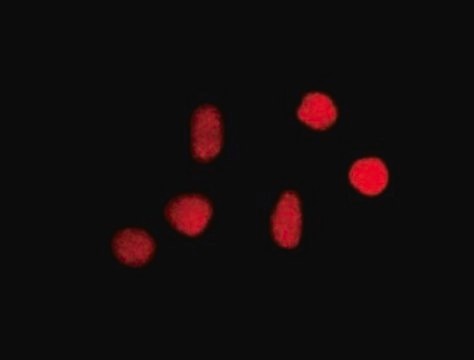

Immunocytochemistry:

Confocal fluorescent analysis of NIH/3T3 cells using anti-8-oxoguanine mouse monoclonal antibody.

On HeLa and Cos7 cells fixed with paraformaldehyde. 8-oxoguanine has been localized to the nucleus in nutrient-deprived cells.